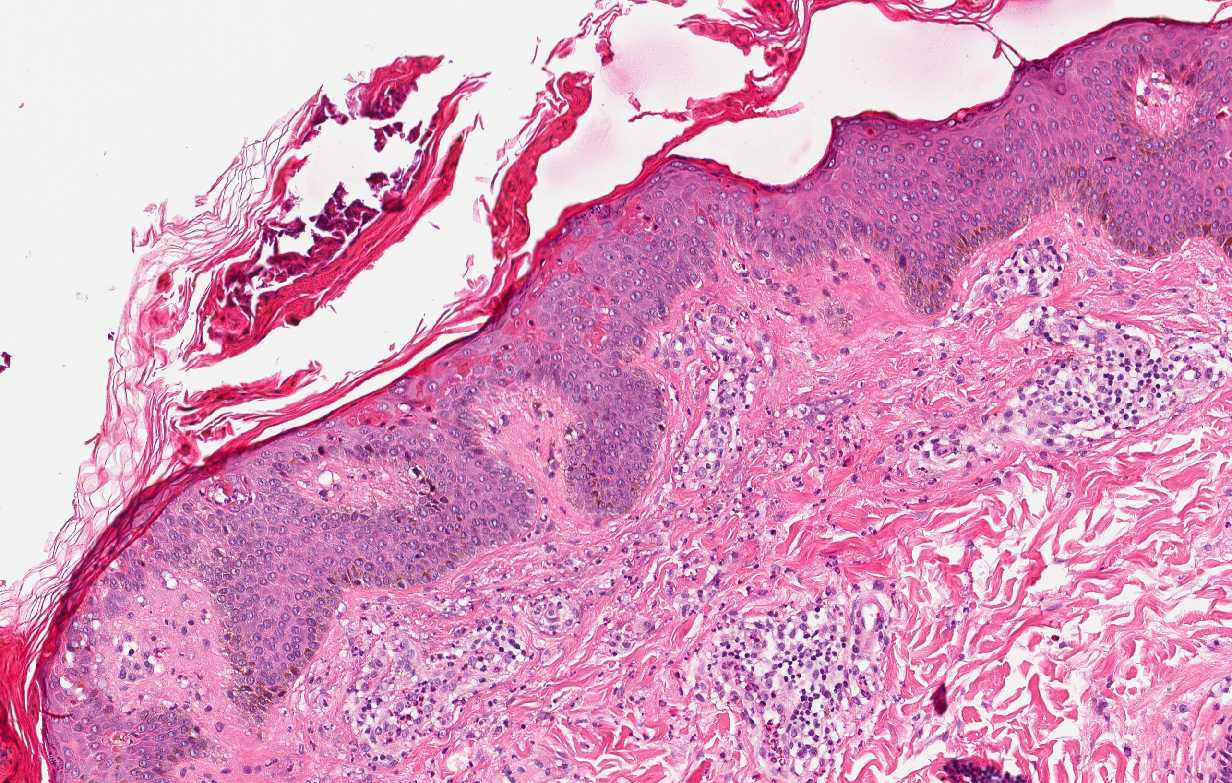

Histologisch worden de persisterende laesies gekenmerkt door heuveltjes van parakeratose en zeer opvallende aanwezigheid van solitaire en/of in aggregaten gelegen necrotische keratinocyten, voornamelijk in de bovenste helft van de epidermis en in de hoornlaag (Figuur 1 en 2). Geringe grensvlak vacuolisatie met sporadische apoptotische keratinocyten, milde acanthose en spongiose worden gezien in ongeveer de helft van de gevallen. Subcorneale pustels of ingedroogde intracorneale pustels en conflurende necrose van de epidermis secundair aan excoriatie komen in een minderheid van de biopten voor. In de dermis wordt meestal een gering tot matig perivasculair en interstitieel ontstekingsinfiltraat gezien met lymfocyten en een wisselende hoeveelheid neutrofiele granulocyten (Figuur 1 en 2). Behoudens pustels is er in de epidermis geen ontstekingsinfiltraat aanwezig [2,4].

Histologisch beeld bij Still's disease Histologisch beeld bij Still's disease